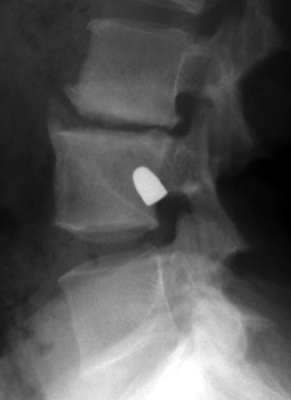

Tumbling Bullet Sign

Post traumatic bone cyst

Two sets of frontal and lateral radiographs, separated only by time, which reveal the "tumbling bullet sign"--which is simply a bullet which changes its location and orientation within a solitary bone cyst. This sign serves two purposes. It is documentation of the evolution of a solitary bone cyst as a corollary of trauma, and reveals the free movement of the foreign body within the confines of the lesion establishing its cystic rather than solid nature. It is similar to the fallen fragment sign.

bulletTaxin RN, Feldman R.: The tumbling bullet sign in a post-traumatic bone cyst. Am J Roentgenol Radium Ther Nucl Med 1975 Jan;123(1):140-3.          [See related articles]